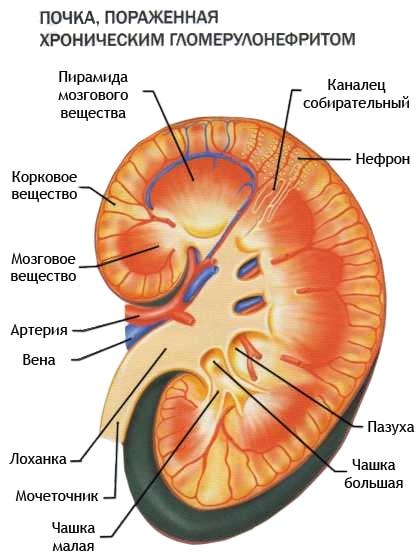

Симптомы подострого гломерулонефрита: фото и описание

Раздел: Визуальный дайджест